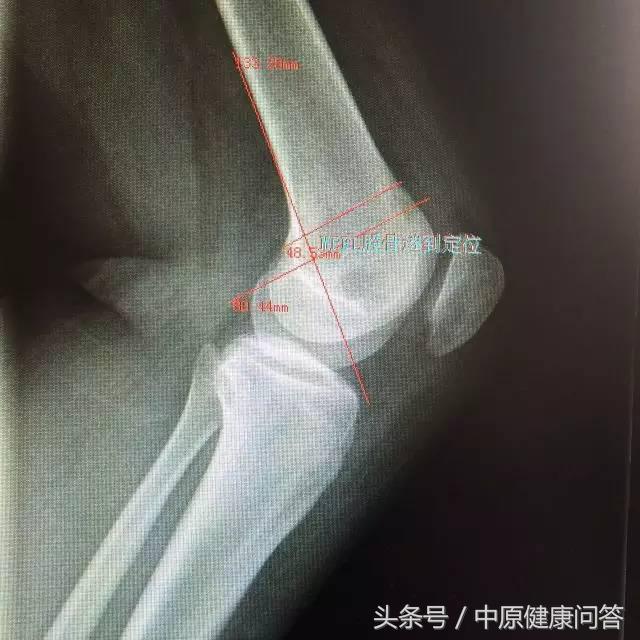

“小芳上一次在当地医院治疗,连一张X光片都没有拍,而我们则对小芳进行了非常完善的体格检查和辅助检查,对髌骨的位置进行了精准的测量,为手术方案的制定做了充分的准备。”负责小芳手术的主治医师邢林卿慎重的说。

DR 检查